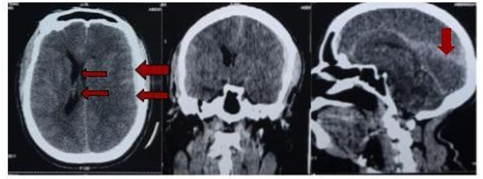

The head CT Scan performed showed a thick left parieto-temporal hyperdensity witha slight midline shift making think of spontaneous acute subdural hematoma (SASH) (Figure 1). The blood investigations (Prothrombin time and Activated partial thromboplastin time; Complete Blood Count; Ionogram; Blood sugar) were normal. Brain angio-CT didn’t show any abnormality (Figure 2). The diagnosis of spontaneous acute subdural hematoma has been retained despite the unavailability of angiography in our context. The patient benefited from conservative treatment under observation (analgesic (combined stage 1 and 2), saline-based fluid intake, osmotherapy for 48 hours, and anti-hypertensive on cardiological advice). The head CT Scan performed 02 days later was unchanged outside a slight remission of meningeal hemorrhage (Figure 3).

Figure 1 Non injected CT showing left fronto-temporal subdural hematoma with midline deviation and subarachnoid hemorrhage.